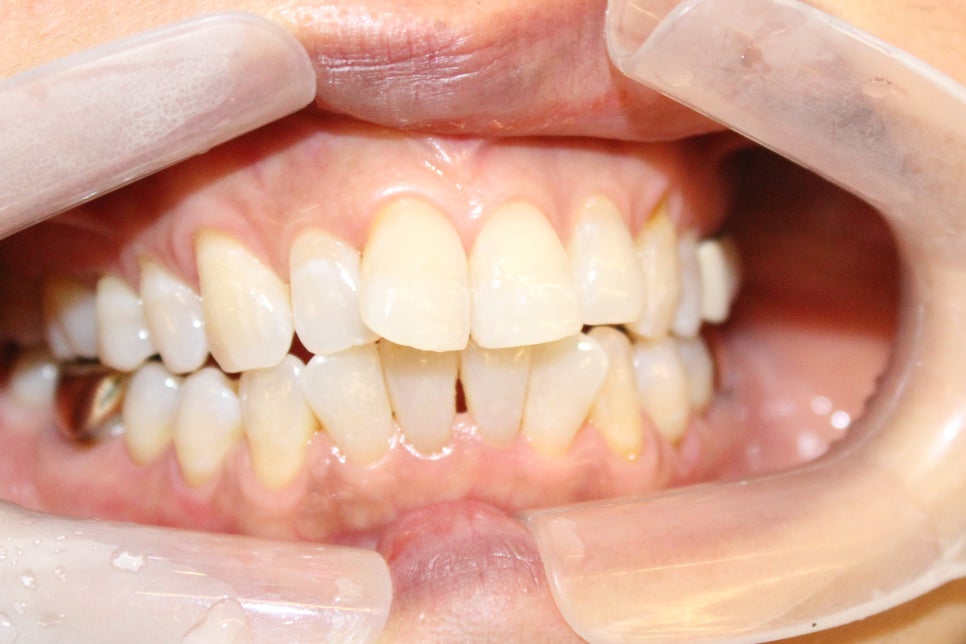

60대 중년여성 진단사진

위의 중년분께서는 몇년 안에 자녀들 결혼을 시키셔야 되는데

좀더 예쁜 모습이었으면 좋겠다고 하시면서 돌출입 교정을 하시고 계십니다.

이분 케이스는 앞니만 부분적으로 교정하시는 것은 한계가 있어서 지금 전체교정을 진행중에 있으십니다.

머지 않아 바로 위의 사진처럼 중년 돌출입을 가지셨던 분께서도 아주 예뻐지실 거예요.

지금도 많이 들어가서 아주 만족하게 진행하고 계시답니다.